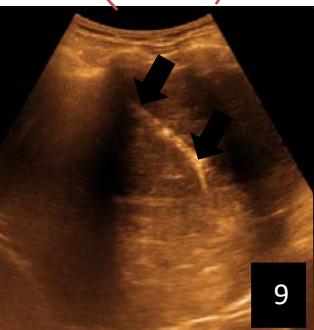

Iconography 1: 54-year-old patient with an intra-splenicsolid mass, anatomopathologically compatible with lymphoma: images 1 and 2: right pleurisy of moderateabundance, image3: celiacadenopathy, image 4: free ascites of moderateabundance, images 5 and 6: intra-splenicsolid mass of around $1418.16\mathrm{ml}$ in B mode and elastographyshowing areas of tumourrigidity, images 7-10: oblique linear images, showingbiopsy gun tracks.

Iconography B: 1 to 4: ultrasound images in mode B showing a large size, 5: ultrasound image in mode B showingsolidhyperechogenic nodules under the capsulorhexis, 6 to 10: ultrasound images in mode B showinglinearhyperechogenic images without overlay in relation to the trajectories of the aiguilles of biopsy.